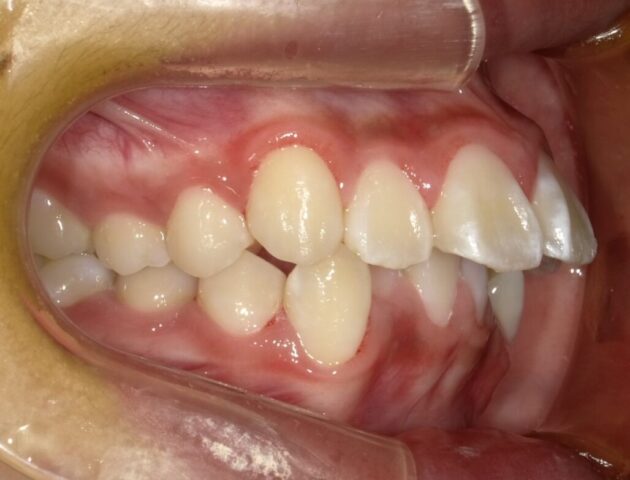

2024年6月(12歳8ヶ月)

永久歯揃いました。

本人のやる気がでたら

2段階目スタートします。